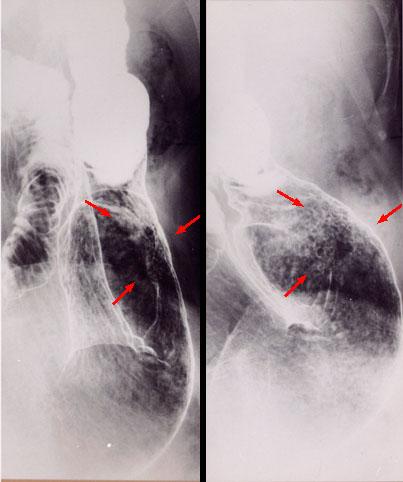

A case of gastric amyloidosis resembling IIc type early gastric cancer.

Inflammatory or ulcerative disease / lesions/Amyloidosis

Stomach/Antrum

X-ray